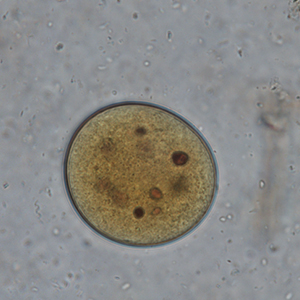

Le kyste est sphérique à ovoïde, à paroi épaisse, mesurant 50 à 100 μm de diamètre. Il présente un contenu granuleux, un macronucléus et micronucléus difficilement visibles (Strait et al., 2012). La coloration au Lugol permet de mettre en évidence certains organites qui apparaissent en brun sombre, de colorer la paroi en brun et l’intérieur du kyste en jaune.

L’identification du kyste de Balantidium coli est en général assez aisée, puisque peu d’éléments ont une morphologie proche.